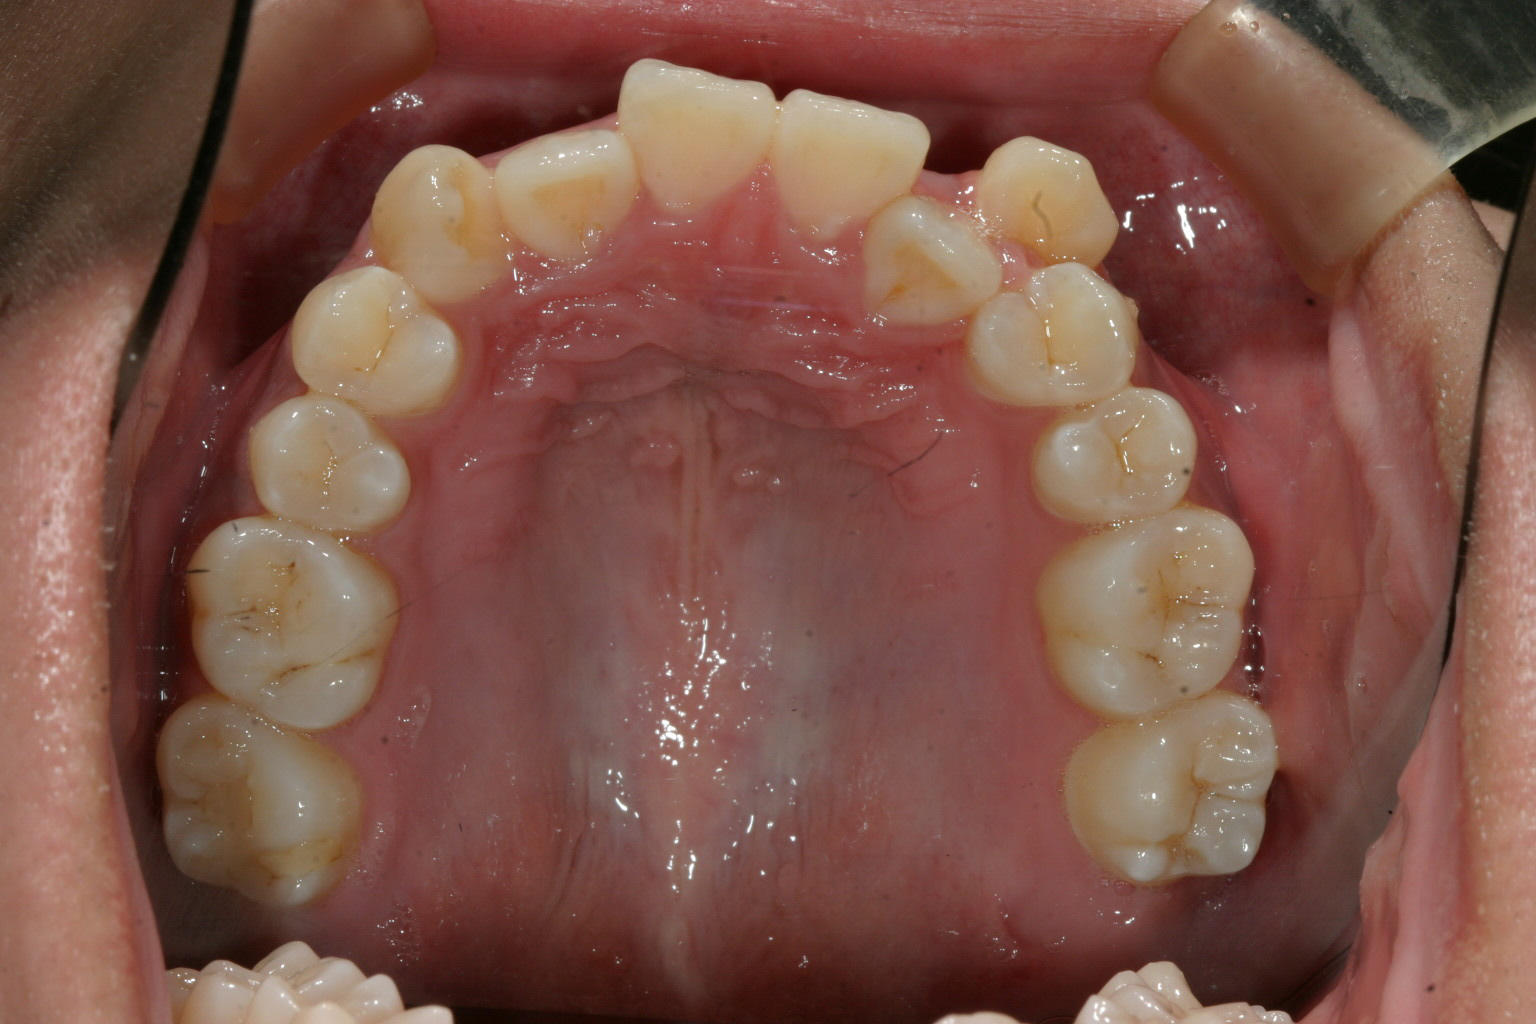

左の犬歯が完全にはじき出されています。

前歯部に叢生が見られます。